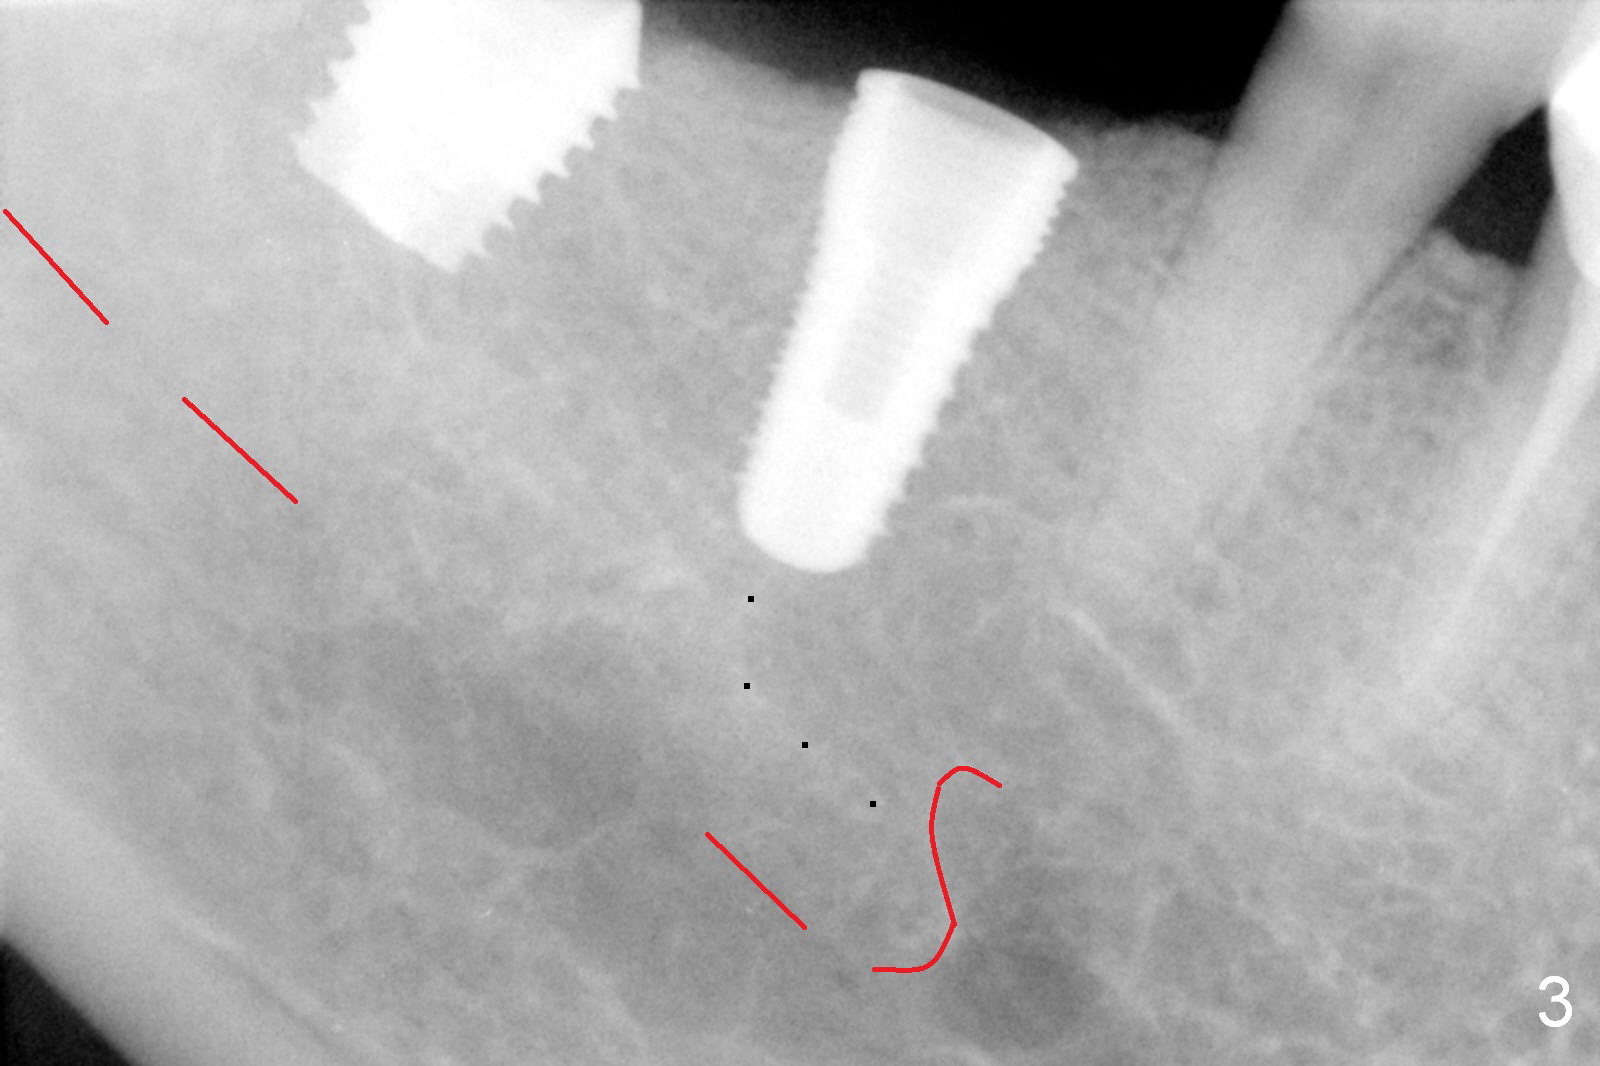

After vacation, the nervous patient returns for #30, 31 implant placement. After infiltration anesthesia, initial osteotomy goes on smoothly at the depth of 10 and 8 mm, respectively (Fig.1). Depth gauge post 5x10 mm drilling shows that the distal osteotomy at #30 is 14 mm in spite of depth control (using drill stopper). Damage the Inferior Alveolar Canal or Mental Loop? Since hemorrhage is moderate, a 5x10 mm submerged implant is placed without discomfort from the patient (Fig.2); when the osteotomy at #31 is being enlarged with 2/2.7 mm pilot drill at 8 mm, the patient experiences severe pain without any obvious reason. The infiltration anesthesia is increased with Articaine and Marcaine. The depth of the osteotomy reduces at 6 mm. The osteotomy and 5.9x6 mm implant placement is done in a slow and gentle manner (Fig.3,4). The bone density mesioapical to the implant at #30 is low (Fig.3 dot line, Fig.5 (CBCT, ≤50 units) *)). This may account for apparent increase in the osteotomy at #30. The soft bone gives in to the depth gauge!

How to explain pain and discomfort of osteotomy and implant placement at #31 in spite of large clearance from the Inferior Alveolar Canal (Fig.3 red dashed line)? Still the low bone density theory. The low bone density (Fig.5 * at #31) makes it easy to transmit the heat and vibration associated with the osteotomy to the underlying nerve!